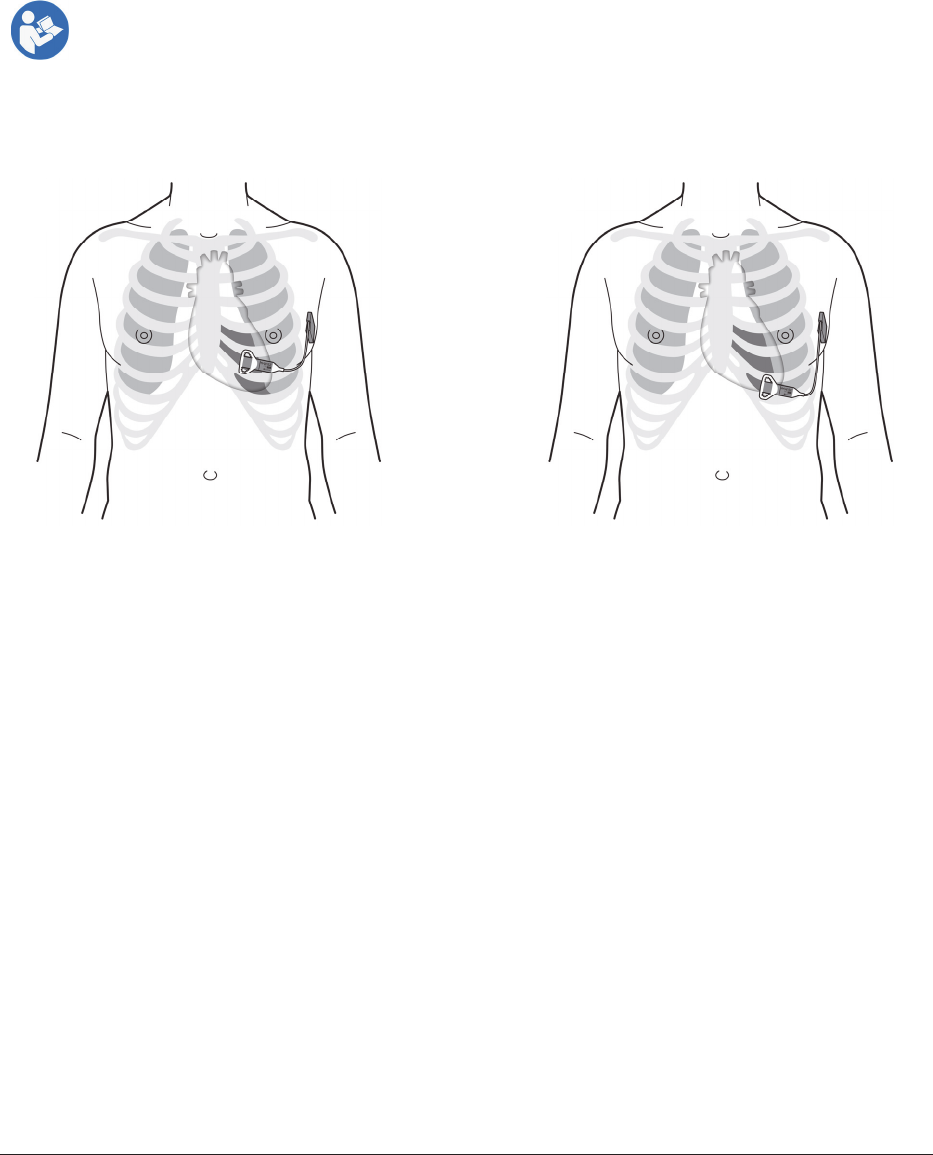

Figure18reflectsgeneralpositioningfortheTransmitterandBattery.TheTransmitterpositionwillbedependent

ontheselectedICS(typicallyinthe5thor6thICS,occasionallythe4thor7thICSmaybeused).Thecablemustexit

theTransmitterpositionlaterally.TheBatterypositionistypicallyalongasuperior/inferiordirectiononthemid‐

axillaryline.

Figure18:TypicalpositioningfortheTransmitterandBattery

A

B

OR

ICS 5

ICS 6